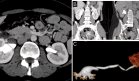

La tomografía computarizada mostró una hiperostosis lobulada con un patrón tubular serpiginoso hipointenso en la meseta tibial lateral y la cara lateral de la diáfisis tibial proximal, hallazgos característicos de melorreostosis.